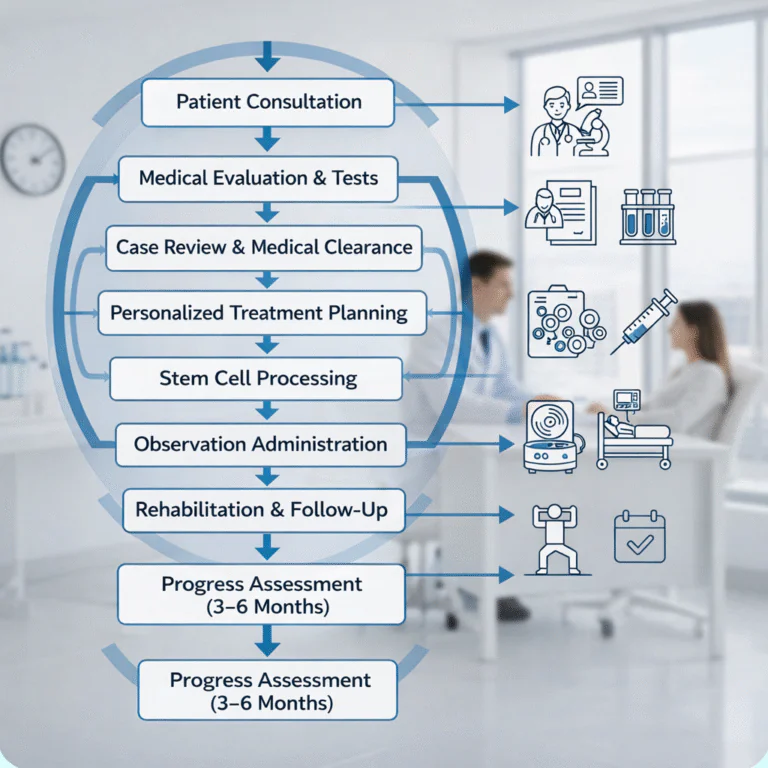

STEM CELL THERAPY

How We

Perform

Therapy

How We Perform

Stem Cell Therapy

at Rekosh Healthcare

Step 1 – Consultation

We begin with a detailed discussion about your medical history, symptoms, and previous treatments. Your reports are carefully reviewed.

Step 2 – Diagnostic Evaluation

We conduct necessary blood tests, organ function tests, and imaging studies to assess your condition and ensure safety.

Step 3 – Eligibility Confirmation

Our medical team reviews all findings to determine if stem cell therapy is suitable for you.

📊 Regenerative Therapy Flow Chart

Stem Cell & Regenerative Therapy Program